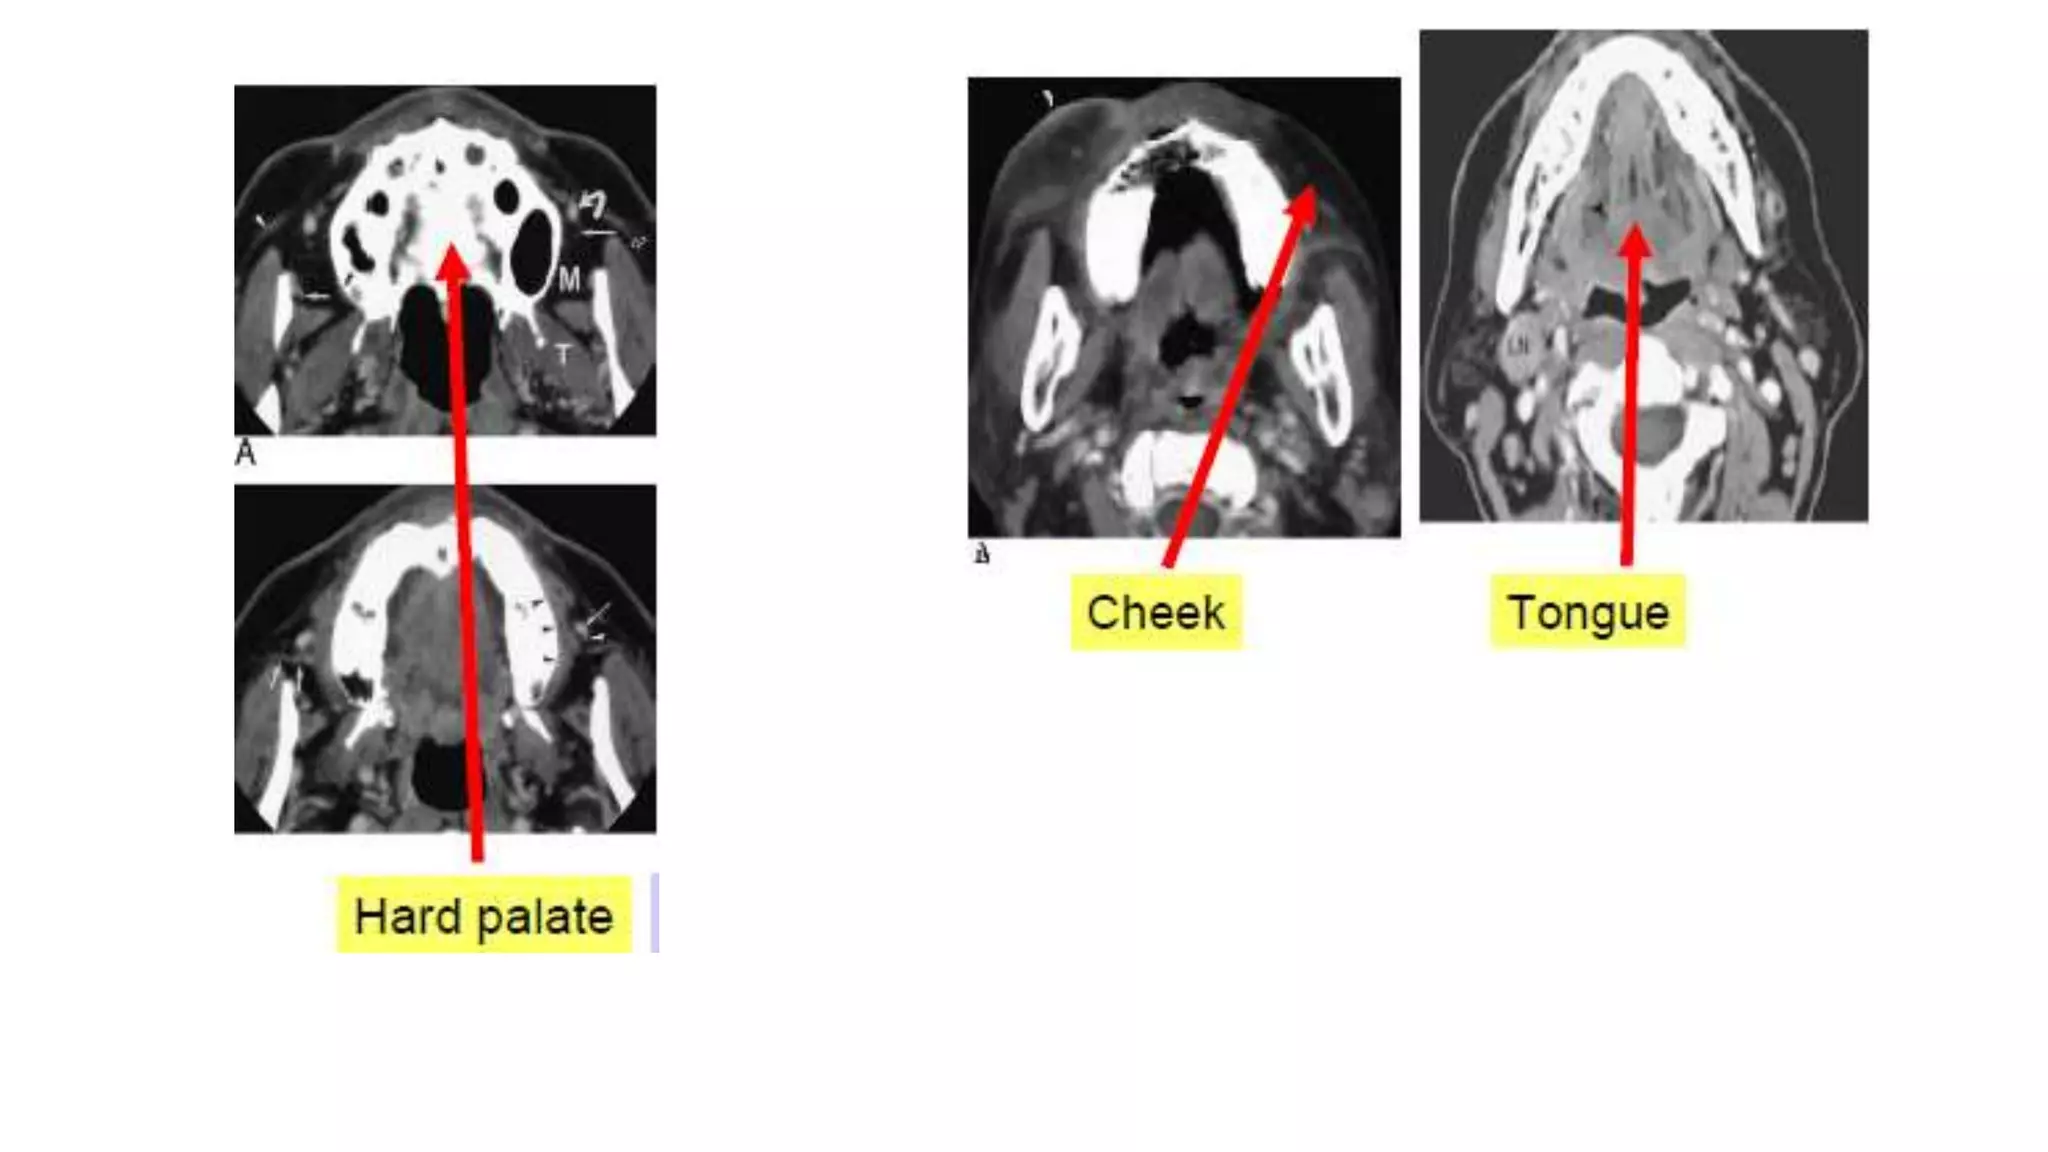

• CT is complemented by the puffed cheek technique (PCT), when oral cavity lesion suspected.

• PCT involves voluntary blowing of the oral cavity with air during the CT. Compliance with the technique is variable,

Puffed Cheek Technique

T

ALV

HP

BM

FOM

Retromolar trigone